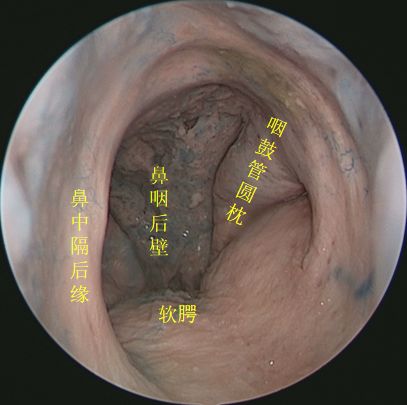

↑ 去除鼻中隔观察鼻腔后壁结构

抵近观察左侧右鼻孔 ↓